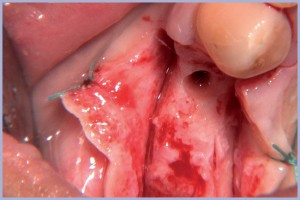

Paziente di sesso femminile di anni 46 in buone condizioni di salute con episodi pregressi di epilessia. La paziente presentava malattia parodontale avanzata, causa determinante le estrazioni degli elementi 1.4, 1.5, 1.6, 1.7 (fig. 1). Dopo tre mesi dalle estrazioni l’arcata superiore destra rimane edentula (figg. 2, 3). Si procede all’esecuzione di un lembo con incisione crestale e di rilascio distale (fig. 4). A seguire, lo scollamento del lembo (figg. 5, 6). Con una fresa a lancia intercettiamo il sito implantare 1.4 che presenta spessori sottili (fig. 7).

- Fig. 4